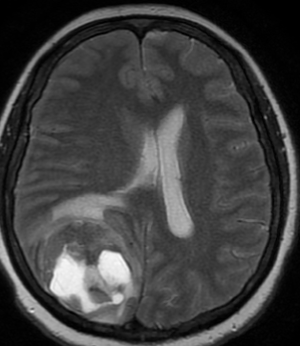

МР-диагностика опухолевого поражения головного мозга или метастазов в головной мозг